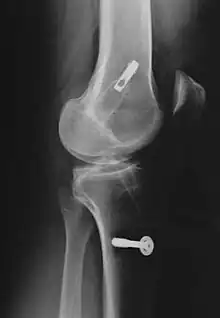

Le décollement ou l'arrachement du LCA de l'os est substantiellement plus rare que la rupture intraligamentaire[5] et n'est pas une rupture de ligament. Ce cas particulier survient plus fréquemment chez les enfants, particulièrement dans le domaine du tubercule intercondylaire du tibia, et possède en général, par refixation de l'arrachement par exemple avec des vis ou des fils métalliques, de bonnes chances de guérison complète.

Les radios n'apportent aucune contribution immédiate au diagnostic de rupture de LC. Les deux LC sont invisibles à la radio, déchirés ou non. La seule utilité de la radio ne peut servir qu'au diagnostic des complications osseuses possibles.

Pour la reconstruction du LC par transplantation autologue au moyen du tendon patellaire, une partie de celui-ci est prélevée avec des morceaux d'os aux extrémités, technique dite bone tendon bone (os tendon os), ou technique BTB. Il est tiré à travers des canaux élargis (8 à 10 mm de diamètre dans le tibia et le fémur). La longueur de chacun des blocs osseux est de 20 mm. L'ancrage le plus stable de la greffe est obtenu par fixation avec des vis d'interférence. Celui-ci est particulièrement important en vue d'une mobilisation fonctionnelle rapide.

Consolidation du transplant

Au début des années 1990, les transplants de tendons patellaires étaient fixés avec des vis d'interférence en titane soit aux deux bouts du transplant, soit uniquement au tibia, et fixés au fémur par un endobouton, enfilé sur le transplant. L'endobouton consiste en une bride de fil non résorbable munie d'une tête basculante en titane (plaque à quatre trous), que l'on bascule après un enfilage à travers le canal dans l'os[238]. Plus tard, on a utilisé des bioscrews (vis d'interférence résorbables) à la place des vis en titane[239], pour rendre une nouvelle opération d'enlèvement des vis inutile. Ces vis sont faites de polymères décomposables, comme un polylactide : Poly-L-lactide ou PLLA, ou poly-L-co-D/L-lactide ou PLDLLA. On peut aussi utiliser une technique hybride de vis résorbables (fixation intra-articulaire) et d'endobouton (fixation extra-articulaire). Dans la Press-Fit-Technik-Fixation, qui naît vers 1995, on peut complètement abandonner la fixation par les vis dans la technique BTB. Les extrémités osseuses sont usinées en cône, si bien qu'un bord-à-bord solide dans les canaux forés est possible. En 1996, on a utilisé des fraises commandées par robot pour faire ce joint, mais ce procédé n'a pu s'imposer en raison de son coût (en personnel et en appareils) et du manque de résultats indiscutablement meilleurs en opération.

Pour les transplants semi-tendineux et gracile (STG), on utilise le plus souvent des vis biodégradables pour la fixation. Depuis la fin des années 1990, on utilise aussi dans ce cas une fixation sans implantation[240]. Dans cette technique, le transplant semi-tendineux et gracile est noué à un bout. Le canal fémoral est creusé 4 mm plus étroit du côté articulation que de l'autre côté. Le transplant est alors introduit dans l'articulation à travers le canal fémoral. Là, le nœud du transplant se coince avant la partie plus étroite. Les mesures ont montré que la rigidité de l'articulation et la charge maximale atteignent des valeurs semblables à celles d'autres techniques. Par le nœud des bouts du tendon, les vis d'interférence deviennent superflues. Les partisans de cette fixation sans vis y voient un avantage de coût. Comme on n'utilise pas de vis, il ne peut pas y avoir de problème avec leurs matériaux[240]. Un inconvénient est cependant le canal significativement plus grand dans le fémur[1].

Pour la fixation des transplants avec des vis d'interférence, il est important que la fixation soit effectuée tout près des surfaces articulaires pour éviter l’effet bungee (le bungee est le saut à l'élastique ; dans le cas présent, il faut éviter que l’élasticité du tendon amène à des frottements longitudinaux contre l'os et à son usure) et l'effet d'essuie-glace (même remarque pour les frottements transversaux à la sortie de l'os)[241].